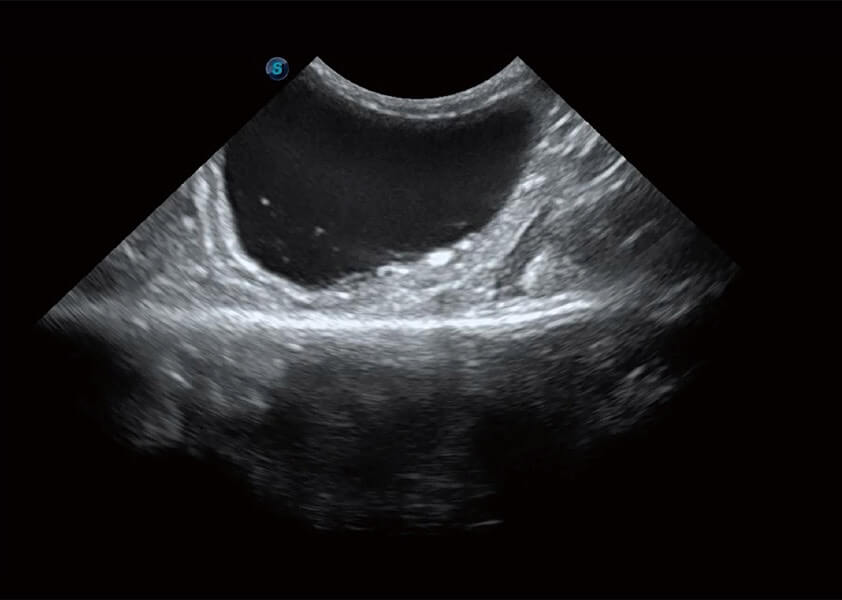

ProPet 60 作为一款高端台式动物超声设备,为动物医生的日常诊断提供了一系列贴合动物临床需求、解决临床实际问题的高级成像功能。凭借全系列高清探头,满足医生对腹部、心脏、生殖、浅表、肌骨等成像的所有需求,切实帮助您提升检查效率,提高诊断信心。

动物是人类最亲密的朋友和最值得信赖的伙伴。美狮贵宾会官网也一直致力于探索动物专用的超声影像解决方案。 全新推出的ProPet系列,是美狮贵宾会官网在动物超声影像智能化、专业化、精准化的一次跨越式革新。动物不能用言语来表述自己的不适,通过超声影像,ProPet系列搭建了动物医生与不同物种沟通的“桥梁”,为动物医生注入了“治愈之力”。